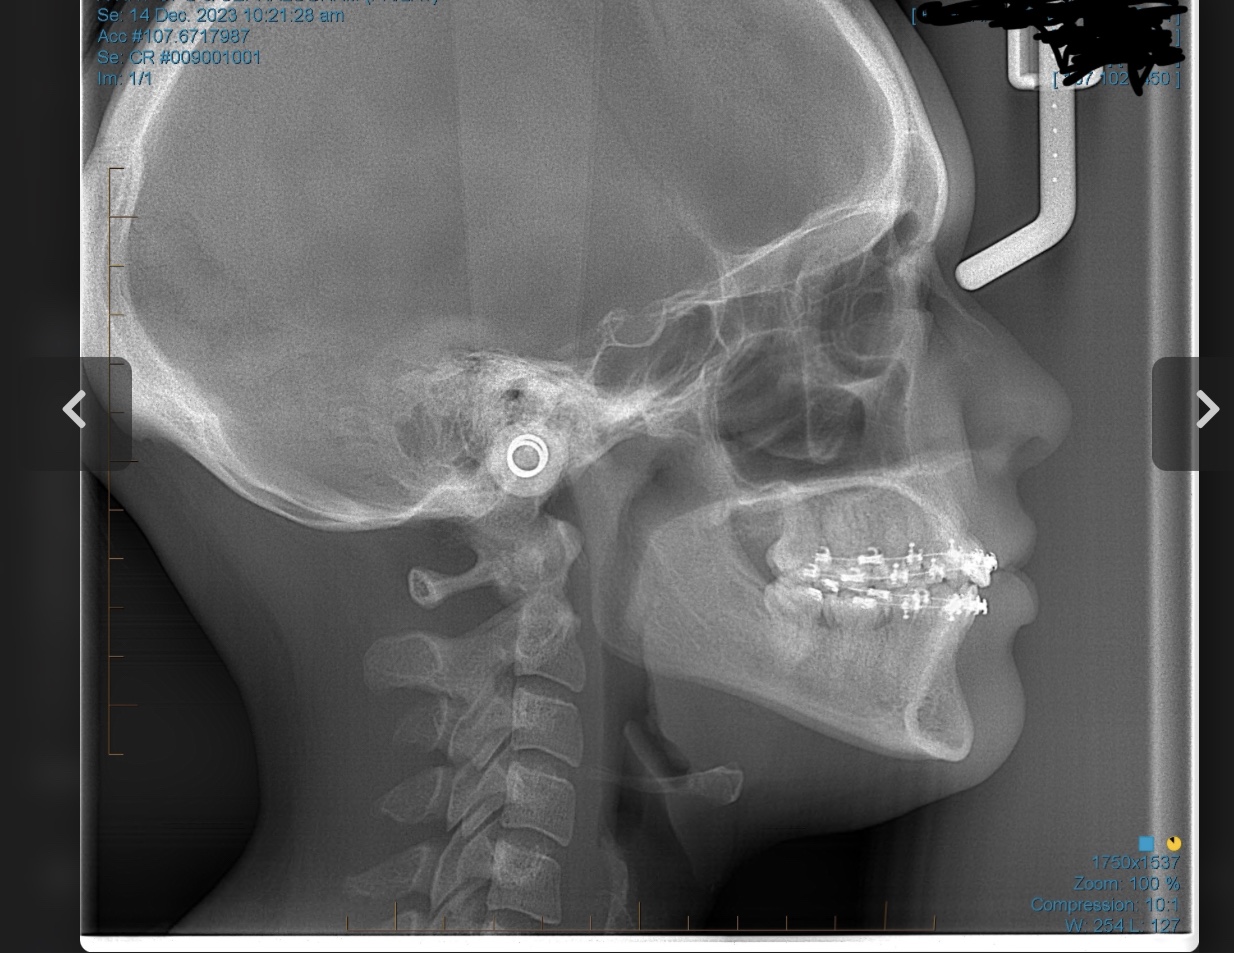

sfs, no ramus and zygos, retrusive, low hyoid, crossbite, crooked/slanted and retracted maxilla, mandible asymmetry, right side of face grown more than left, 8 extractions at 13 (including premolars).